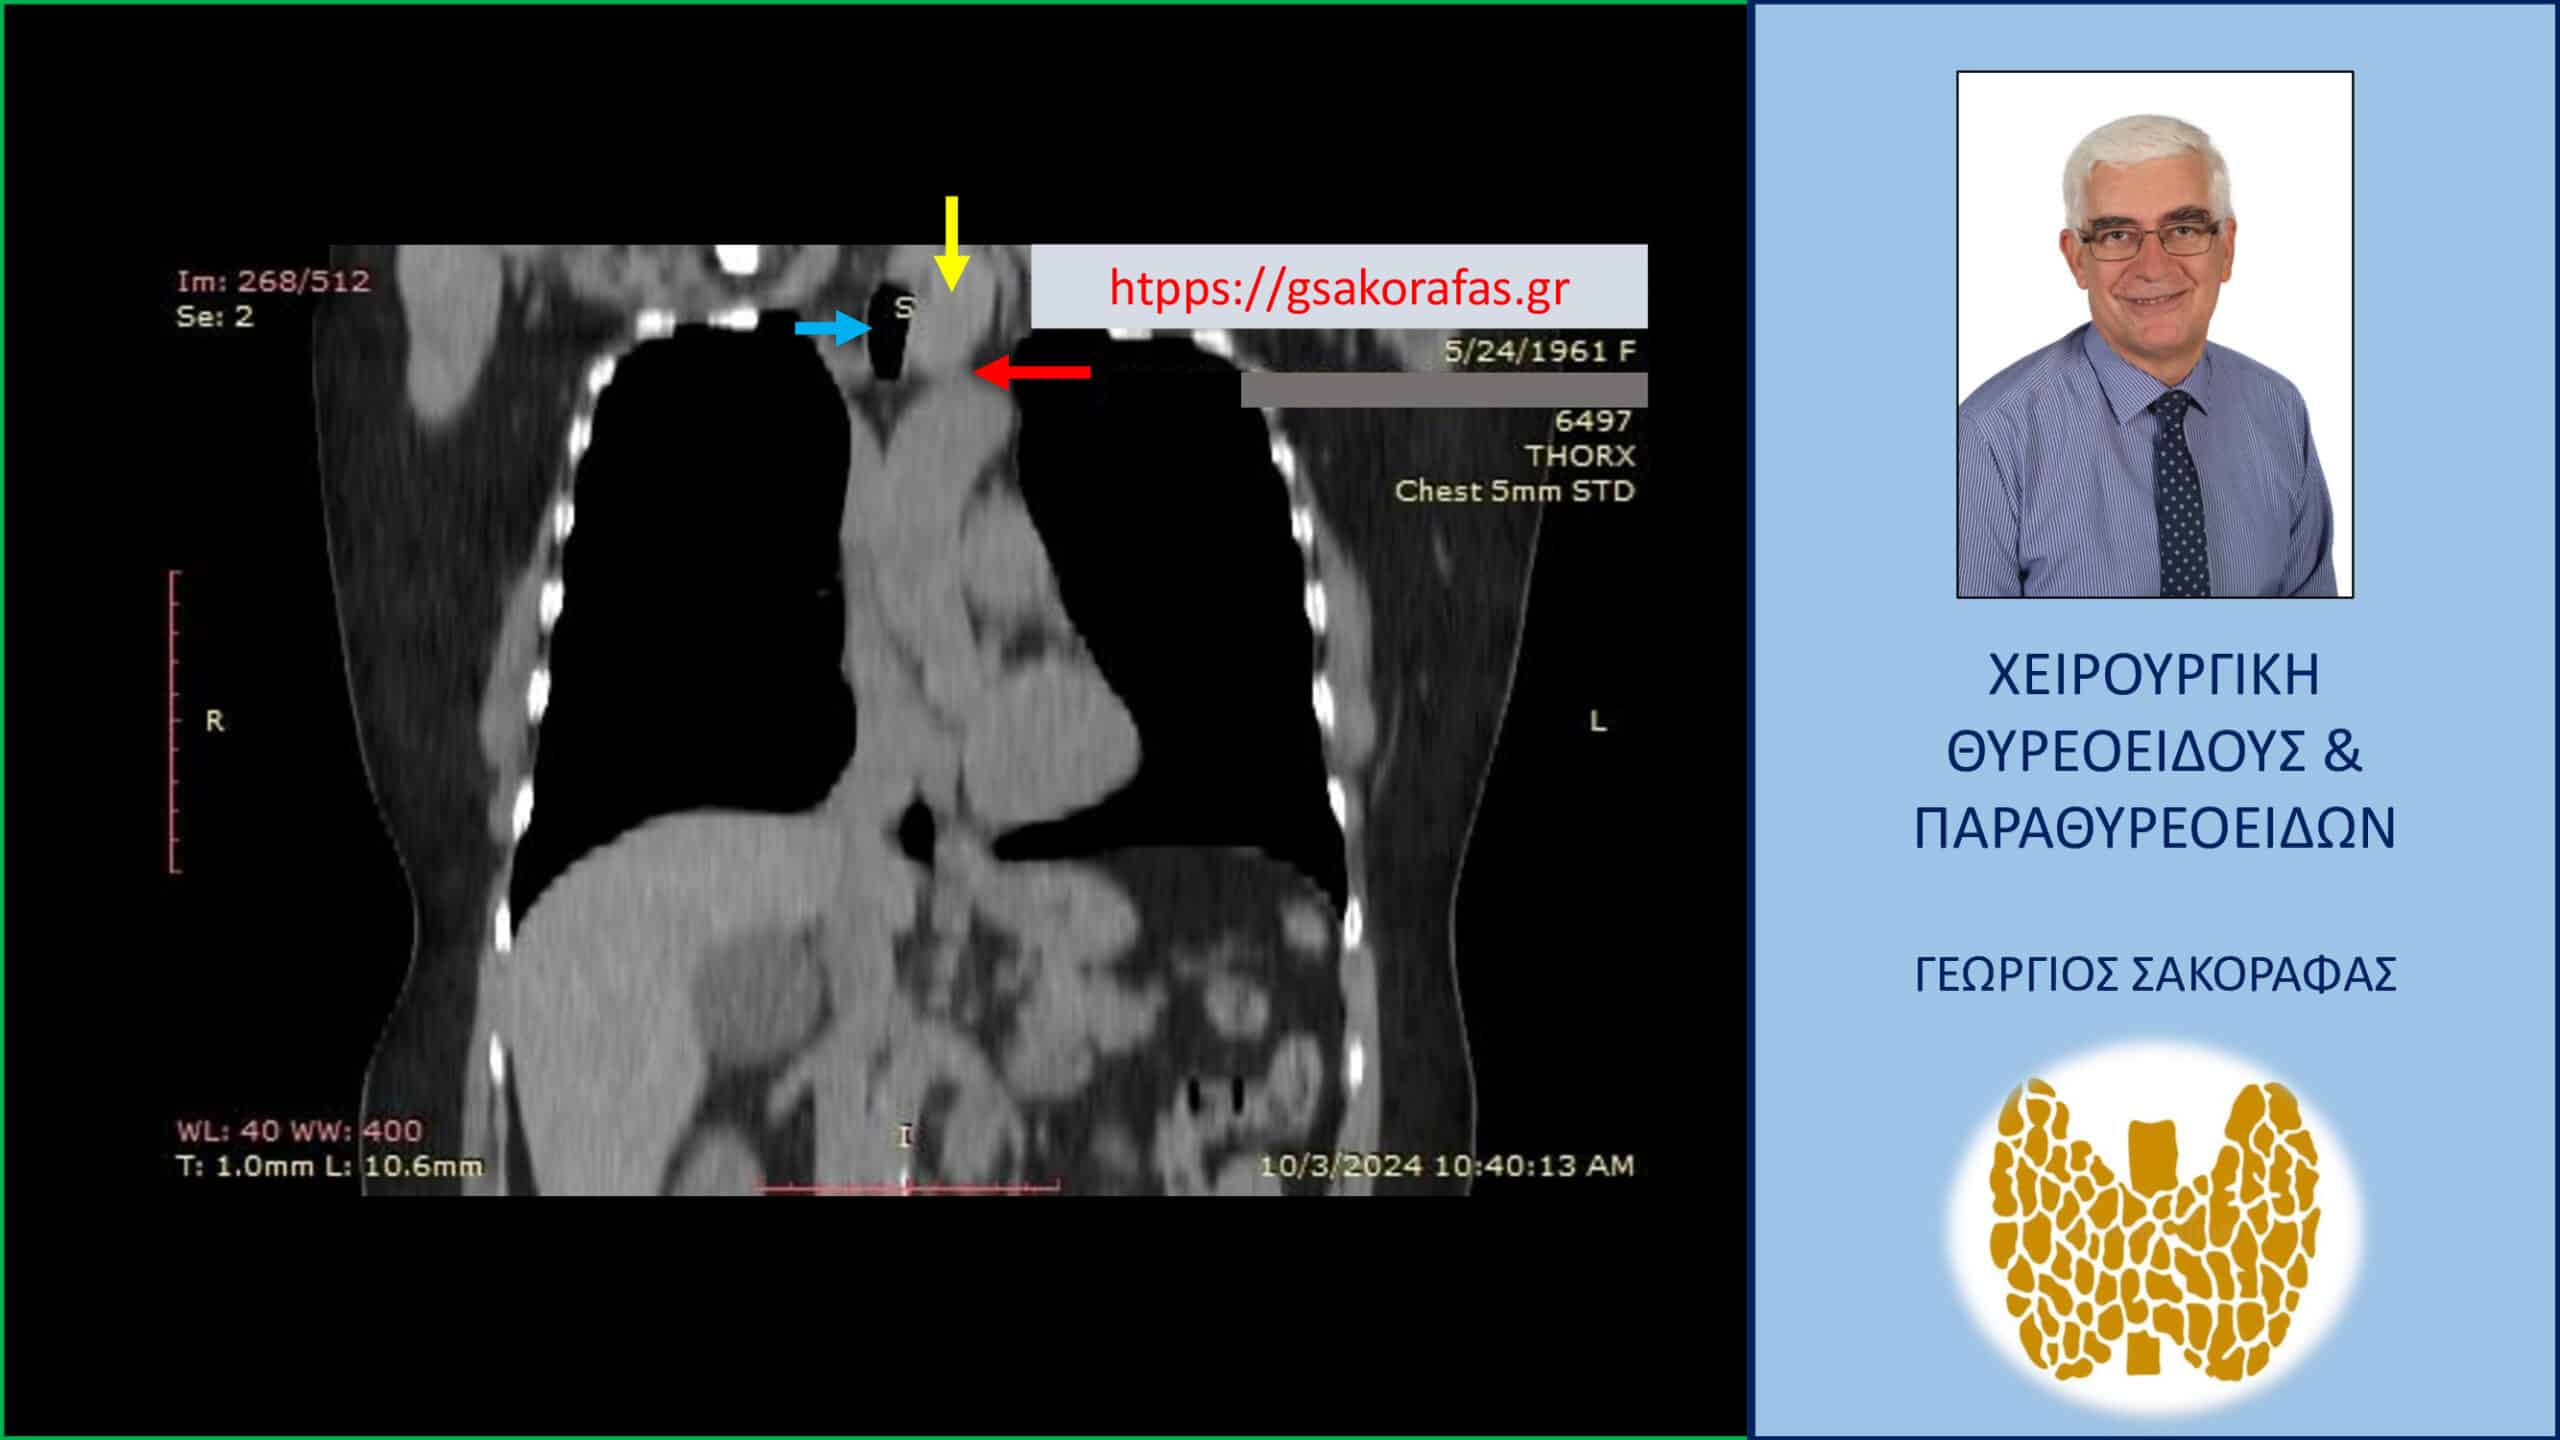

Παρατηρείται ο διογκωμένος αριστερός λοβός με την παρουσία όζου εντός αυτού. Ο λοβός παρουσιάζει κατάδυση μέχρι το ύψος της παρυφής του αορτικού τόξου και προκαλεί απώθηση της τραχείας προς τα δεξιά (βλ. εικόνες).

Όζος θυρεοειδούς καταδυόμενος αριστερά . Απεικόνιση στην αξονική τομογραφία – στεφανιαία διατομή. Εμφανής ο διογκωμένος αριστερός λοβός του θυρεοειδούς (κίτρινο βέλος) που καταδύεται στο μεσοθωράκιο μέχρι τις παρυφές του αορτικού τόξου (κόκκινο βέλος). Η τραχεία (μπλε βέλος) πιεζόμενη από τον καταδυόμενο αριστερό λοβό του θυρεοειδούς απωθείται προς τα δεξιά.

ΕΙΚΟΝΑ 2. Απεικόνιση στην αξονική τομογραφία – στεφανιαία διατομή. Εμφανής ο διογκωμένος αριστερός λοβός του θυρεοειδούς (κίτρινο βέλος) που καταδύεται στο μεσοθωράκιο μέχρι τις παρυφές του αορτικού τόξου (κόκκινο βέλος). Η τραχεία (μπλε βέλος) πιεζόμενη από τον καταδυόμενο αριστερό λοβό του θυρεοειδούς απωθείται ελαφρά προς τα δεξιά.